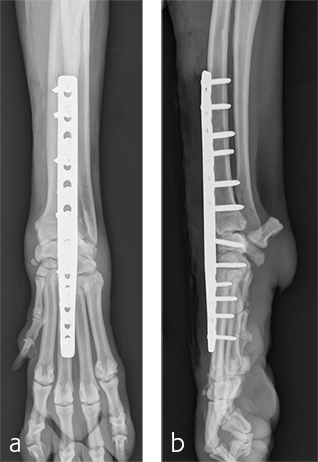

Treatment with a splint for several weeks resulted in no improvement. A pancarpal arthrodesis was performed with the 2.7/3.5 Pancarpal Arthrodesis Plate and a combination of standard cortical and locking screw fixation. An autogenous cancellous bone graft was collected from the left proximal humerus and placed at all joint levels.

Immediate postoperative images confirmed anatomic alignment and adequate carpal extension (Fig 10). At the 11-week postoperative follow-up examination, functional recovery was very good with images revealing stable implants and healing of the arthrodesis (Fig 11). The dog was then allowed to return to normal activity.